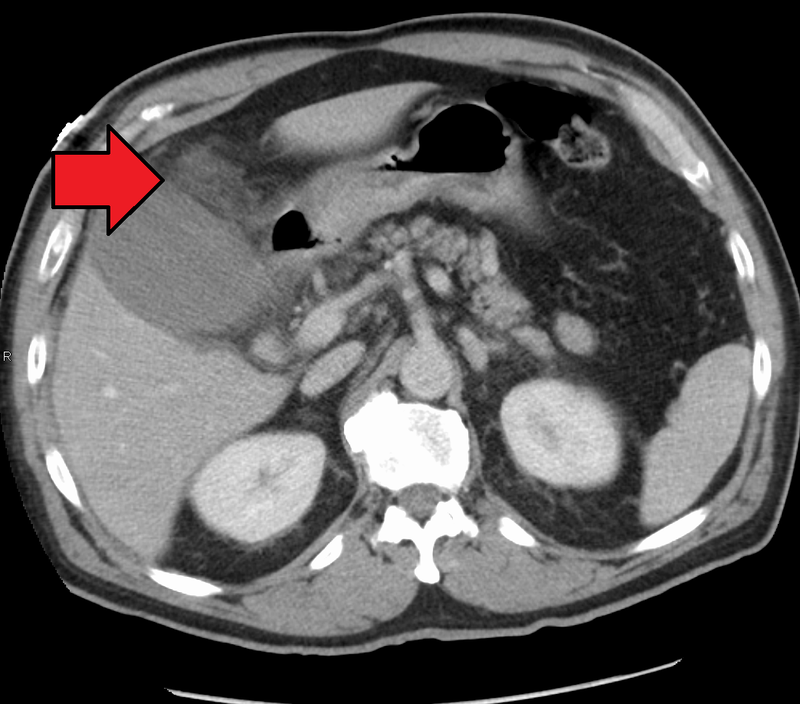

Acute cholecystitis is inflammation of the gallbladder wall.

Acute cholecystitis may be due to an impacted stone in the cystic duct that causes inflammation, bacterial overgrowth (E. coli), and dilatation with pressure ischemia.

If acute cholecystitis is not treated there is a chance for gall bladder rupture.